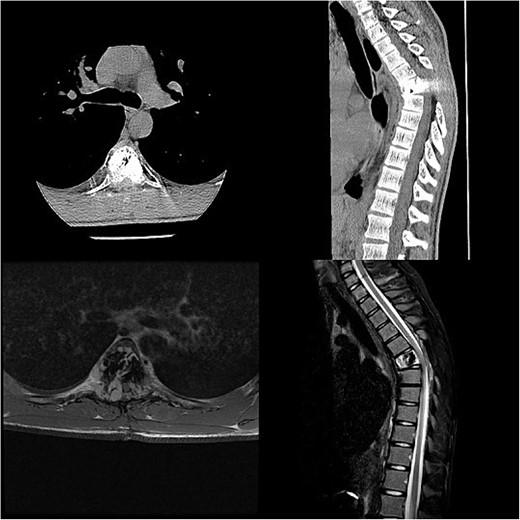

Three and a half years prior to admission to our institution, the patient underwent emergent Th6 vertebroplasty with laminectomy for a radiologically characteristic and histologically confirmed Th6 AVH causing acute thoracic myelopathy with a week-long paresis of the right foot dorsiflexion, performed by another surgeon. A progressive kyphotic deformity of the Th6 vertebrae was observed on radiographic follow-ups, whereby the hypoesthesia on the right anterior thigh persisted (ASIA score D, VAS pain score 7). Follow-up MRI and CT imaging revealed recurrent AVH of the Th6 vertebrae expanding into the spinal canal, leading to newly recognized worsening of myelopathy (Fig. 1). Additionally, a concomitant haemangioma was observed in the right transverse and articular process of Th8 (Fig. 2).

MRI scan of the thoracic spine showing a concomitant haemangioma in the right transverse and articular process of Th8.